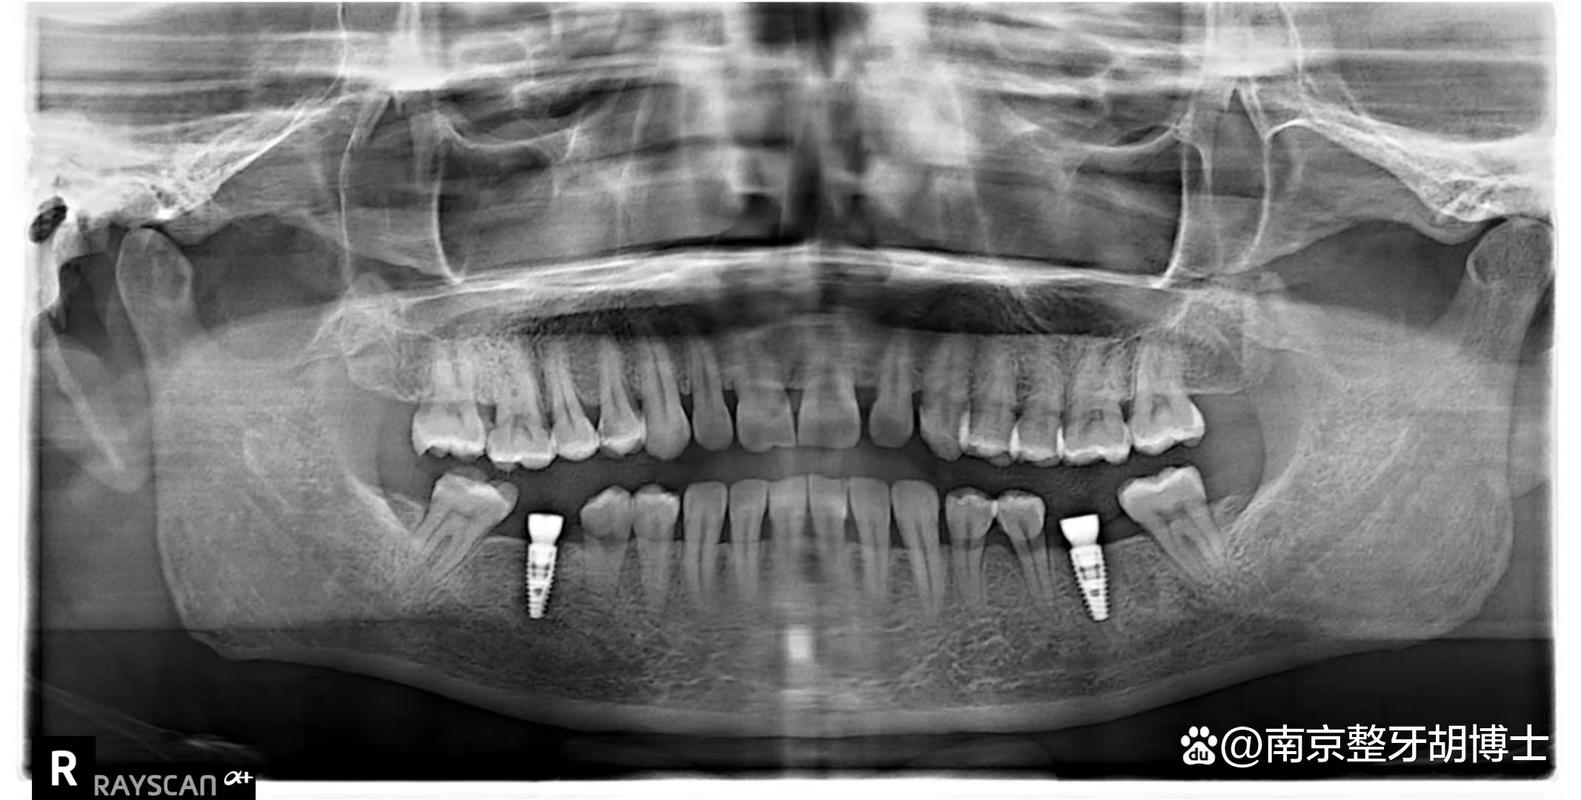

先进设备和优质材料是手术效果的保障,必备设备包括:口腔CBCT(精准评估牙槽骨情况)、数字化种植导板(提高种植精度)、无菌手术室(降低感染风险);种植体建议选择国际知名品牌(如瑞典Nobel、瑞士ITI、德国Ankylos等),或经过国家认证的国产品牌(如百康特、威高),牙冠优先全瓷材质(生物相容性好、美观耐用)。